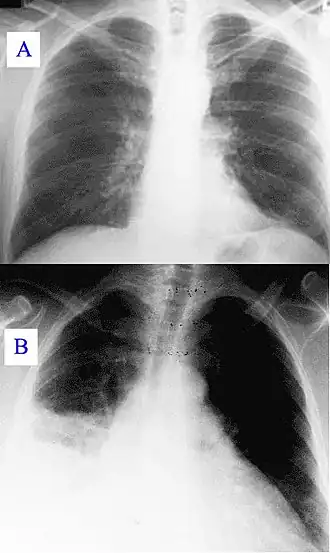

Durante el curso de la infección, la enfermedad puede progresar a una neumonía atípica, la cual puede desencadenar un síndrome de distres respiratorio agudo, tales síntomas usualmente ocurren durante los primeros 4-5 días de infección.